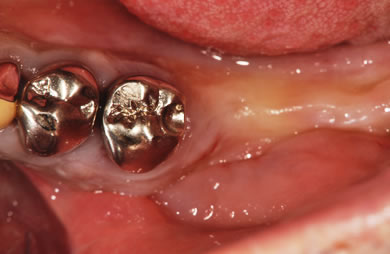

インプラントの症例写真 IMPLANT

スピードインプラント治療+セラミック治療

| 主訴 | 歯茎の腫れと前歯が欠けているのが気になる。 | ||||||||||||||||||||||||||||||||

| 治療方針 | 欠損部位である右下6番とともに、隣接部位の破壊された歯周組織を回復。 | ||||||||||||||||||||||||||||||||

| 治療内容 | インプラント3本(抜歯即日スピードインプラント)、ハイブリッドセラミック3本 | ||||||||||||||||||||||||||||||||